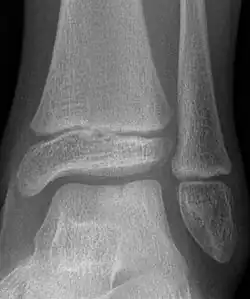

Die Talusspalte (lateinisch Talus bipartitus, englisch talus cleft, split talus oder bipartite talus) ist eine seltene Ossifikationsstörung mit einer bei Geburt vorliegenden Spaltbildung im Sprungbein (Talus), nicht zu verwechseln mit dem außerhalb der Gelenkflächen liegenden Os trigonum.

Grundsätzlich kann ein Spalt in der Sagittalebene oder sehr selten koronar in der Frontalebene verlaufen.[1]

Bildgebend wird die Veränderung bereits im Röntgenbild ersichtlich und kann mittels Kernspintomographie oder Computertomographie genauer dargestellt werden.